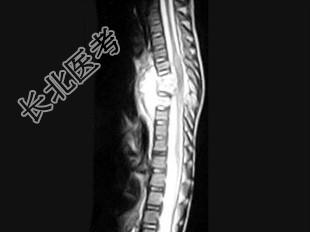

- 单项选择题男,8岁, 咳嗽、咳脓痰,背部肿痛。结合图像, 最可能的诊断是 ( )

E、脊椎结核